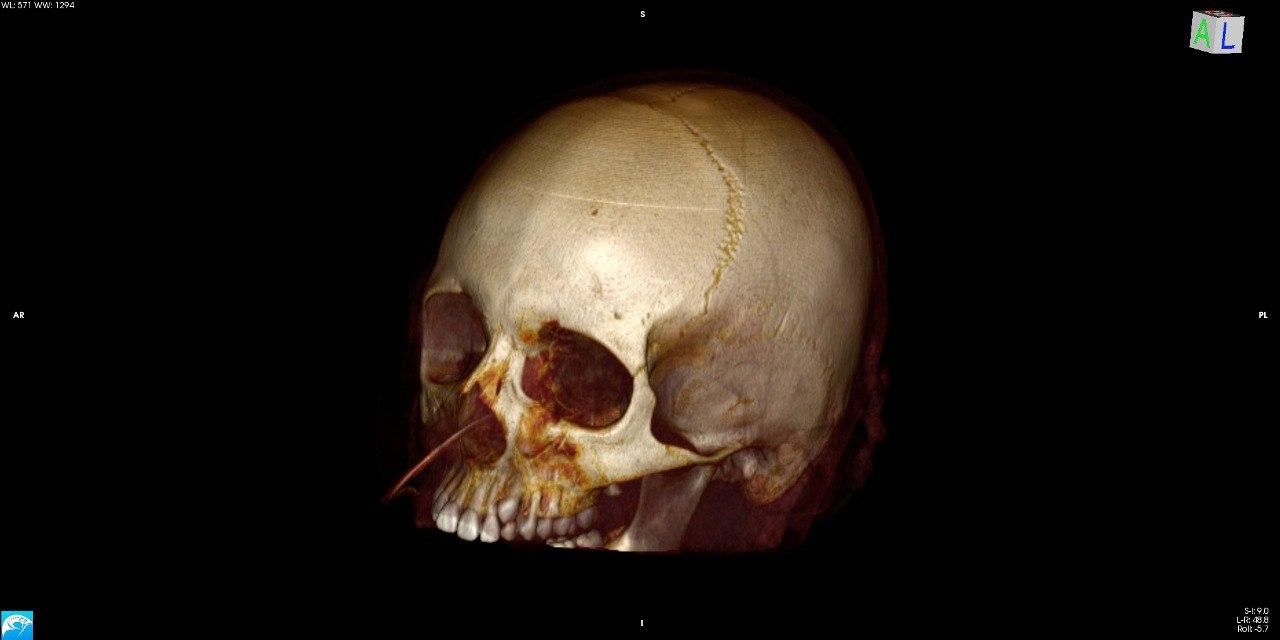

- КТ: створює детальні зображення кісток та м’яких тканин у вигляді “зрізів”. Дозволяє виявити навіть найменші зміни.

Комп’ютерна томографія: Надає детальні зображення внутрішніх органів та тканин, допомагає виявити пухлини, запалення та травми.

- Комп’ютерна томографія: Siemens SOMATOM X.cite (128 зрізів, мах. 364 реконструйовані зрізи)